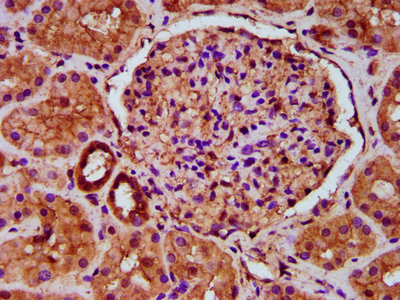

IHC image of CSB-PA803114LA01HU diluted at 1:500 and staining in paraffin-embedded human kidney tissue performed on a Leica BondTM system. After dewaxing and hydration, antigen retrieval was mediated by high pressure in a citrate buffer (pH 6.0). Section was blocked with 10% normal goat serum 30min at RT. Then primary antibody (1% BSA) was incubated at 4°C overnight. The primary is detected by a biotinylated secondary antibody and visualized using an HRP conjugated SP system.